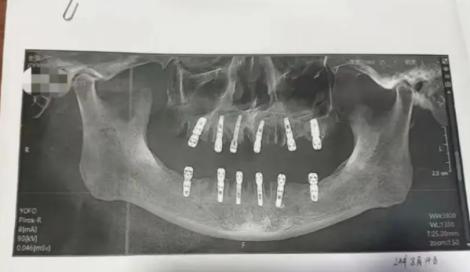

(圖/微博)

黃男的家屬表示,黃男在8月14日在當地「德維口腔醫院」接受牙科手術,共拔牙23顆、植牙12顆,並且均為即刻修復,也就是「當天拔、當天種」,由一名袁姓醫師負責。